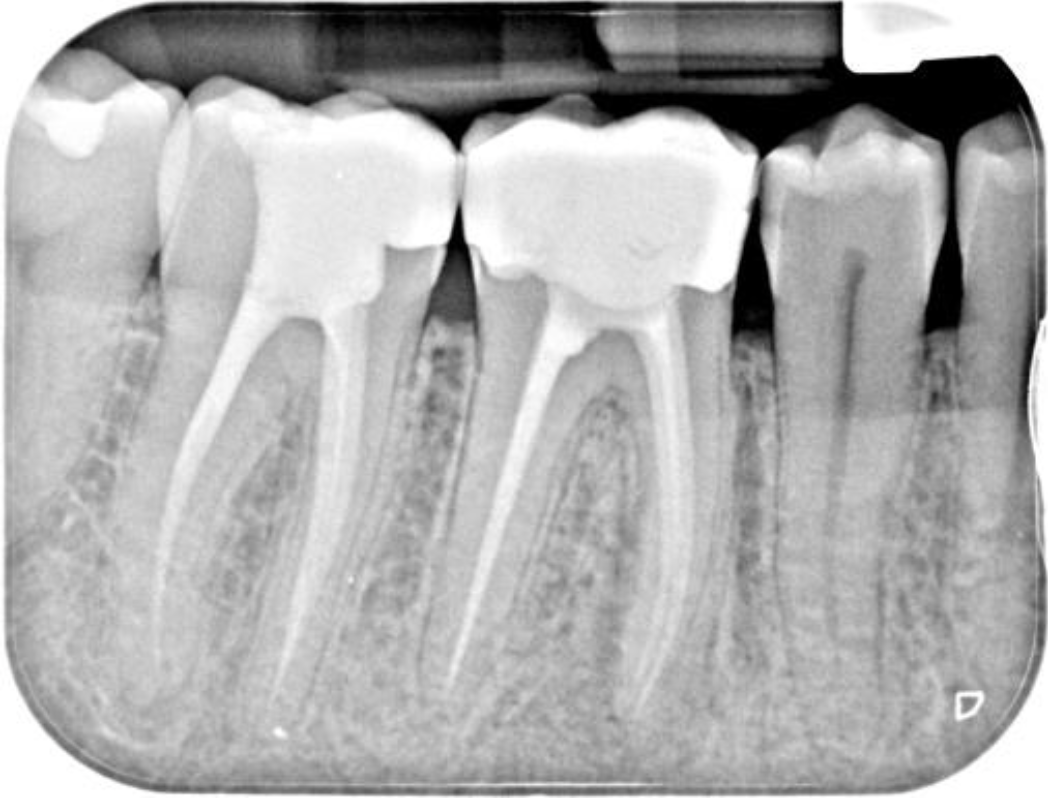

This was an interesting case from a diagnostic perspective. At the consultation appointment, the patient reported previous episodes of poorly localised pain from the LRQ and a recent episode of swelling in this area (not present at the consultation). The RD had managed this with antibiotics. IOPA review indicated that the LR6 and LR7 had been previously root treated (well!), but it was unclear which tooth was problematic. The patient reported that both root treatments were performed approximately 7-8 years ago. As both teeth had large composites in situ, a loss of coronal seal seemed like a possible cause of failure for either root treatment. In an attempt to clarify things and to help reach a diagnosis, we took a small field of view high-resolution CBCT scan of the area (see above). I requested a consultant radiologist’s report on the CBCT scan from JM Radiology with the key findings listed below:

- A significant PARL around the mesial root of the LR6 that extended halfway up the proximal surface.

- There were 4 root canals, 2 mesial and 2 distal. The 2 mesial canals had separate exit portals, and the 2 distal canals exited through a single exit portal (extremely useful information to have when you are planning a re-treatment case)

- No unfilled canal space (or was there!)

- Could not discount a fracture, therefore the patient had to be consented for this.

A diagnosis of failed root treatment with a recent acute apical abscess was made for the LR6. Once this tooth was accessed utilising an operating microscope, the most likely cause of failure was identified and can be seen in the picture below. There were 2 unfilled middle mesial canals not identified by the sca,n and this seemed to explain the pattern of inflammatory change seen around the mesial root. As helpful as CBCT imaging can be in endodontics, this case highlights that CBCT analysis of root-treated teeth does have its limitations. Scatter artefact can often make it quite difficult to see fine detail in such cases, so it’s useful to bear this in mind. This case was retreated using Reciproc Blue R25 and involved copious amounts of irrigation and activation. It was then obturated using hydraulic condensation and Totalfill BC sealer Hiflow. It was then sent back to the RD for cuspal coverage. I have suggested getting a follow-up CBCT scan in 12 months’ time to assess healing and also to review the small radiolucency at the distal apex of the LR7. I will update this case study once I have the review imaging.